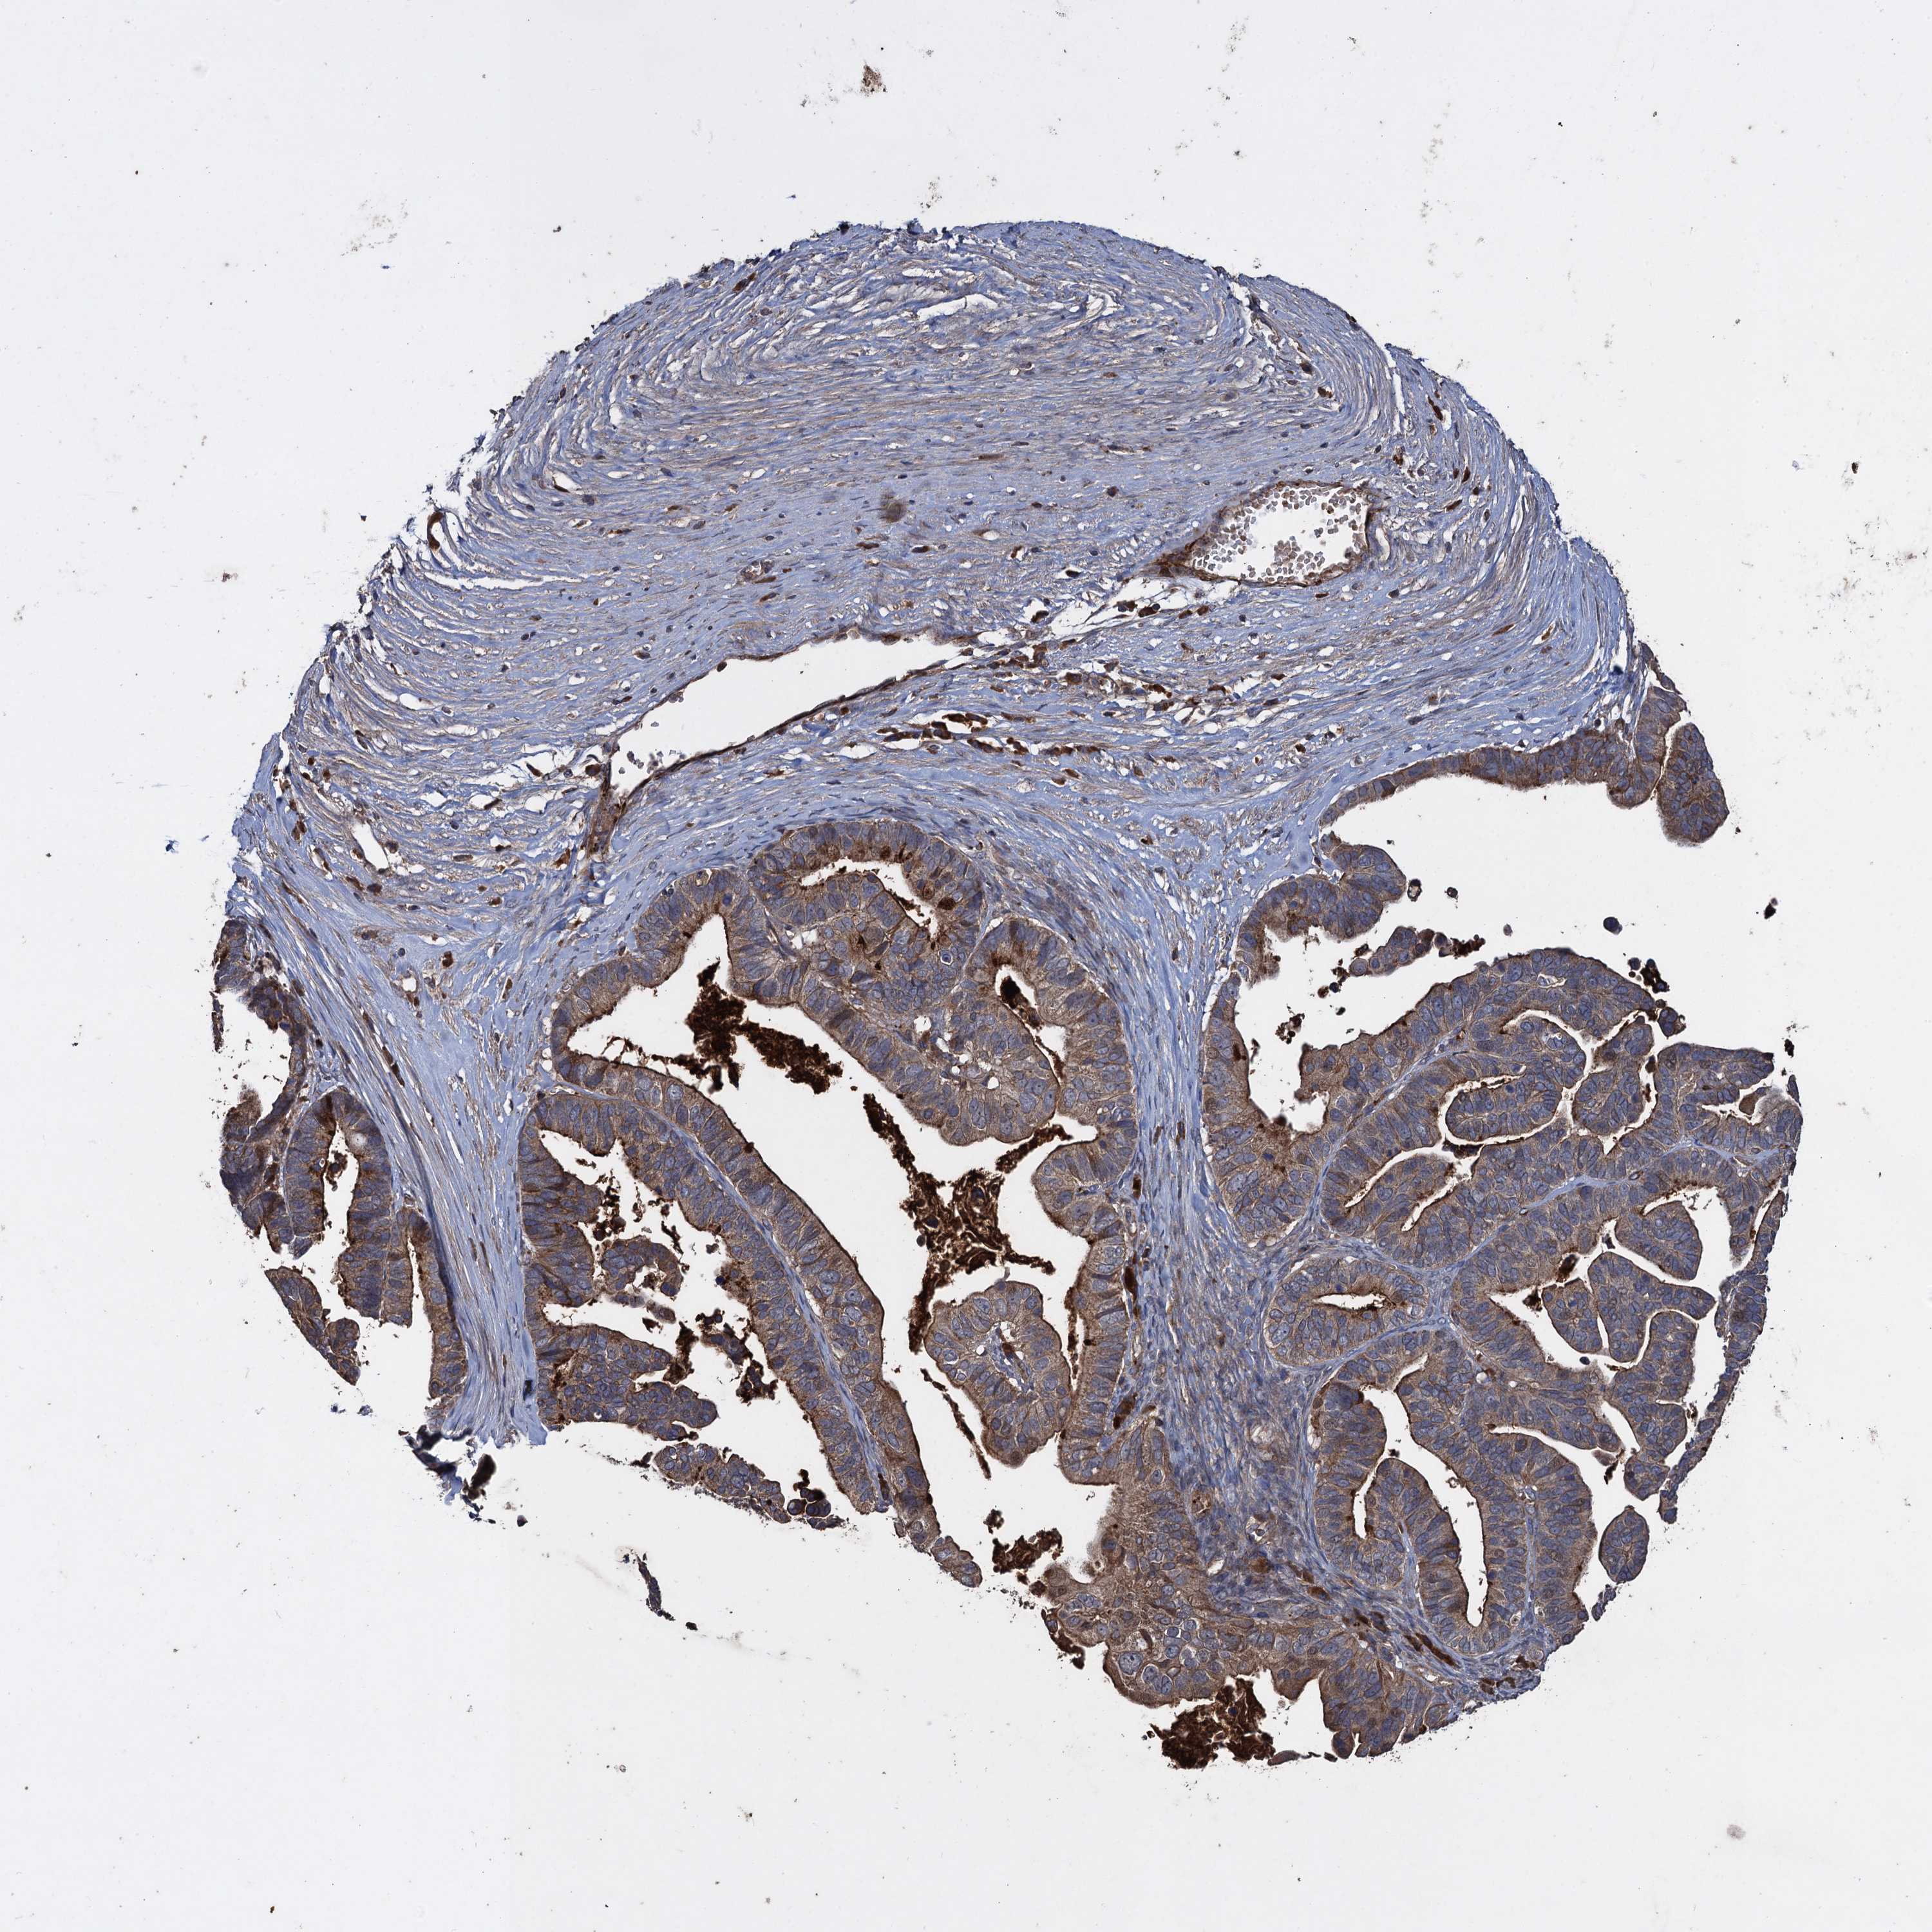

OVARIAN CANCER - Protein expressioni

A mouse-over function shows sample information and annotation data. Click on an image to view it in a full screen mode. Samples can be filtered based on level of antibody staining by selecting one or several of the following categories: high, medium, low and not detected. The assay and annotation is described here.

Note that samples used for immunohistochemistry by the Human Protein Atlas do not correspond to samples in the TCGA dataset.

Antibody stainingi

Antibody staining in the annotated cell types in the current human tissue is reported as not detected, low, medium, or high, based on conventional immunohistochemistry profiling in selected tissues. This score is based on the combination of the staining intensity and fraction of stained cells.

Each image is clickable and will lead to virtual microscopy that enables deeper exploration of all samples and also displays staining intensity scores, fraction scores and subcellular localization as well as patient and tissue information for each sample.

Antibody HPA041174

Antibody HPA041390

Cystadenocarcinoma, serous, NOS

Carcinoma, endometroid

Cystadenocarcinoma, mucinous, NOS

Carcinoma, NOS